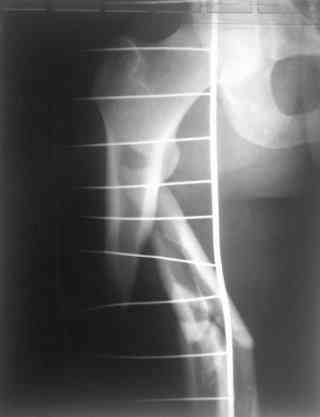

одна проблема в моей компьютерной неграмотности(не смог прикрепить снимки), а другая в том, что связь с пациентом потеряна и,насколько я понял в своем регионе ему посоветоваться не с кем, кроме главного врача который отреагировал на выбранную нами тактику так: "там тебя использовали в качестве подопытного кролика...".

Надеюсь сейчас показать перелом, а потом синтез.